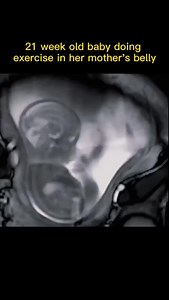

6.3M views · 29K reactions | Do you feel fetal movement when you are pregnant So cute殺 | Parenting Mangi | Facebook